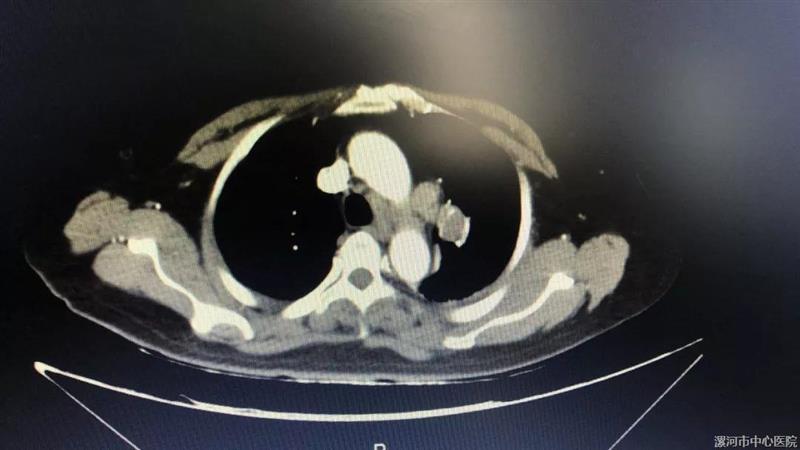

我院成功开展全市首例昏迷患者CT引导下经皮肺穿刺活检术

近日,我院成功为一位昏迷患者实施CT引导下经皮肺穿刺活检术,填补了漯河市此项技术的空白。患者癫痫昏迷 无法明确诊断病情8月25日,神经内科一病区收治了1例因“发作性意识不清、四肢抽搐10天”为主诉入院的病危患者,入院后患者反复出现癫痫发作,伴有精神行为异常,抗癫痫药物治疗效果差,病情危重,随时可能进展为癫痫持续状态,危及生命。术前CT显示右肺大动脉附近有一肿块“患者诊断为自身免疫性脑炎(抗GABABR抗体相关脑炎...

本网 10/08